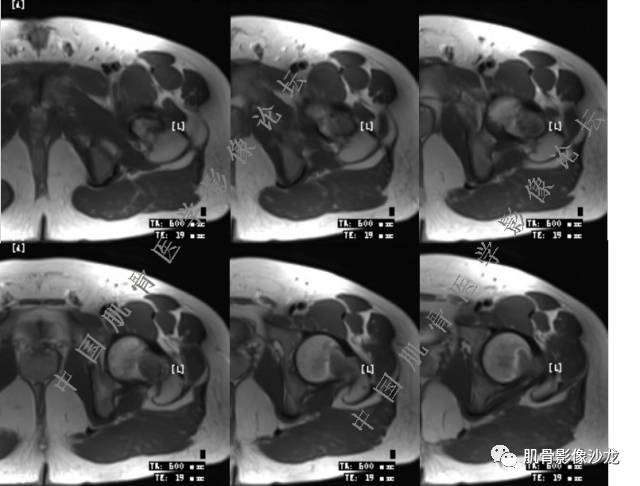

主诉:右侧股骨近端持续疼痛1月余

现病史:1个月前因天气转冷突然右侧股骨疼痛,无乏力麻木,遂就诊于当地医院X线检查发现右股骨异常密度,为进一步诊治来我院。

既往史:高血压史。余无特殊。